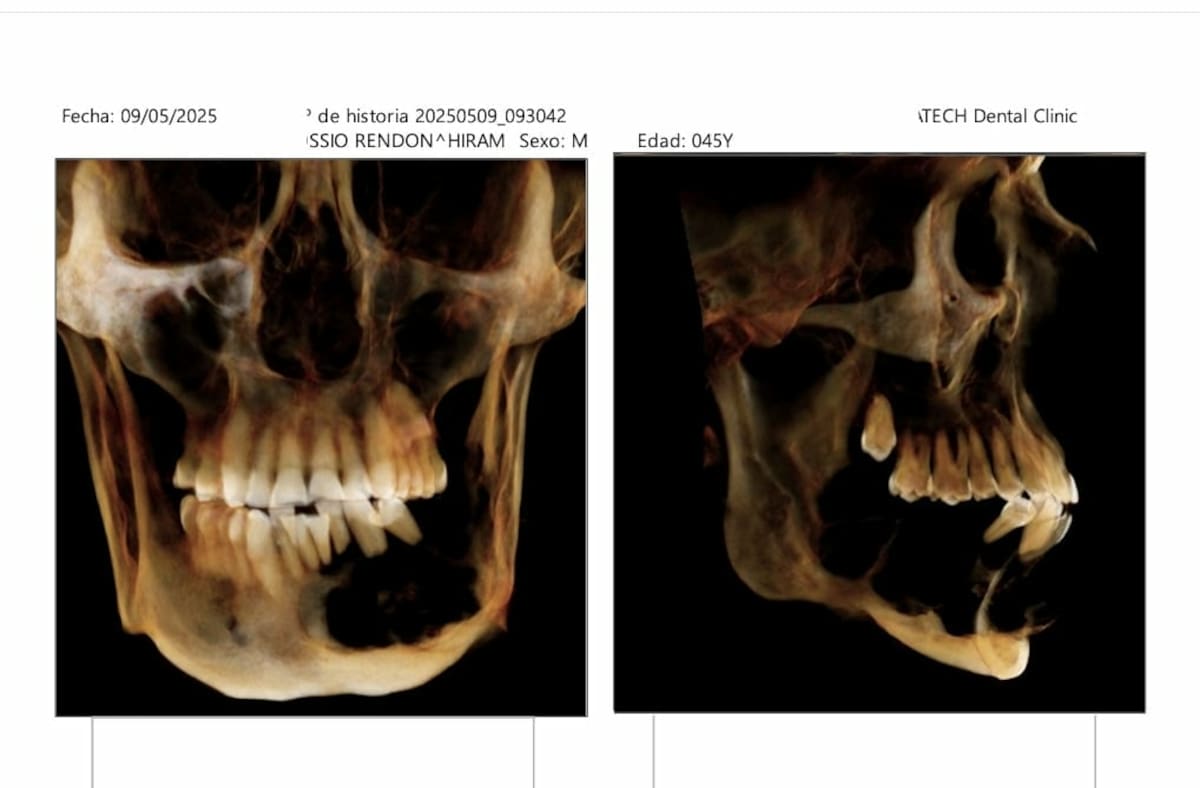

HERMOSILLO, Sonora. — Hiram Kossio fue diagnosticado hace dos años con un ameloblastoma en la zona maxilar inferior, lo que pone en riesgo su calidad de vida al prácticamente deshacer parte de los huesos de su rostro y mandíbula.

El ameloblastoma es un tumor propio de la zona del maxilar; puede ser superior o inferior, pero en el caso de Kossio creció en la parte inferior derecha de su mandíbula.

Esto ha provocado que algunos de sus dientes se muevan, al no tener el soporte del hueso mandibular en esa área, además de que continuamente retiene líquidos, lo que le produce una hinchazón extrema e incomodidad.

Esto es bueno —compartió—, ya que no invadiría zonas vitales como el cerebro o los huesos faciales cercanos a la nariz o los ojos, pero si no se atiende, puede destruir toda la mandíbula. Entonces, hay cosas positivas como negativas”.